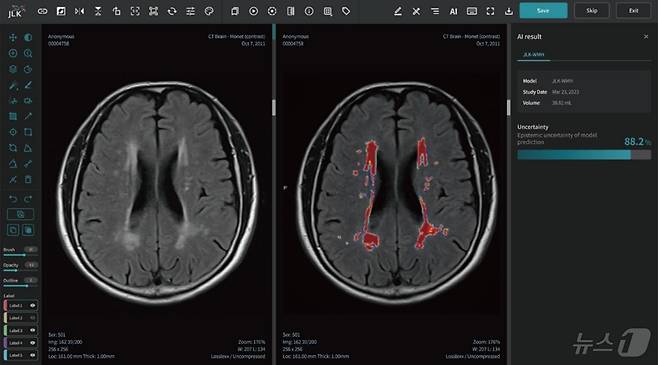

해당 논문에는 급성 뇌졸중 환자 8421명의 MRI 데이터를 AI가 학습하는 방식으로 개발해 만성 뇌허혈 병변에 해당하는 백질 변성(white matter hyperintensity: WMH) 영역을 시각화하고 정량적으로 분석하는 JLK-WMH의 개발 과정과 성능 연구 등이 담겼다.

논문에 따르면 제이엘케이 AI 솔루션은 급성 뇌졸중 환자의 MRI 영상을 분석해 환자의 백질변성 영역을 빠르고 정확하게 탐지하고 정량했다. 특히 10년 이상의 경력을 보유한 전문의와의 정량 분석 일치도가 99%에 달하는 등 영상 데이터를 정량적으로 정확하게 분석해 백질변성과 관련해 발생할 수 있는 치매 등의 퇴행성질환의 조기 진단 및 연구에 널리 활용될 수 있을 것으로 기대된다.